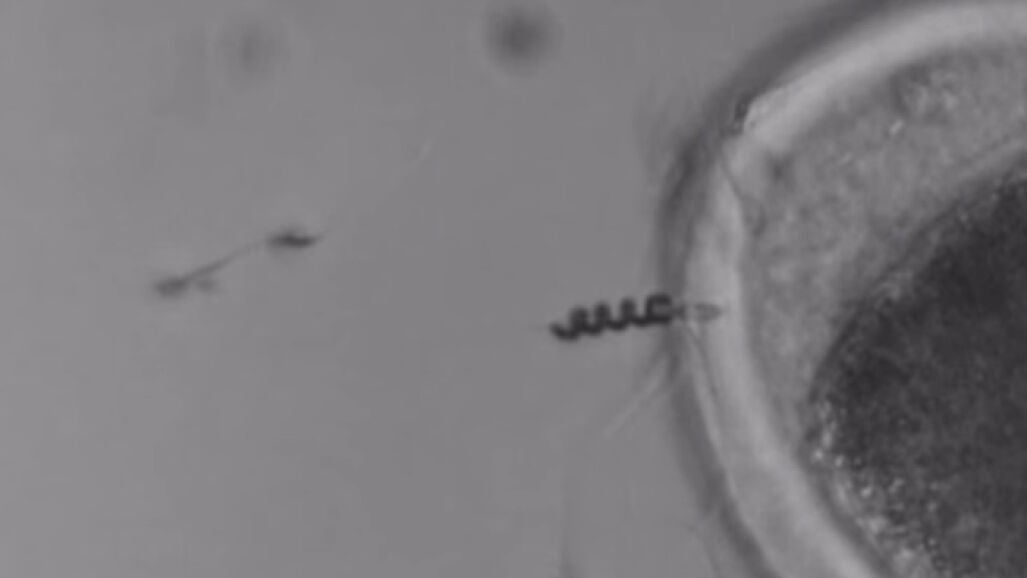

Un equipo de investigadores alemanes ha diseñado una hélice metálica diminuta que, colocada alrededor de la cola de un espermatozoide, le ayuda a alcanzar el óvulo. La mejora de su movilidad permitiría solucionar una de las principales causas de la infertilidad masculina.

Se trata en realidad de unas hélices fabricadas con microtubos de hierro y nanopartículas de titanio que estos científicos del Instituto de Neurociencias Integrativas de Dresden colocan alrededor del flagelo de las células. El resultado es una especie de ‘bots biológicos’ teledirigidos.

Según describen en un artículo publicado en 'Nano Letters', los espermatozoides son impulsados mediante campos magnéticos que los expertos controlan de forma remota. Una vez que alcanzan el óvulo y lo fecundan, las células perderían la funda metálica, capaz de desprenderse por sí sola.